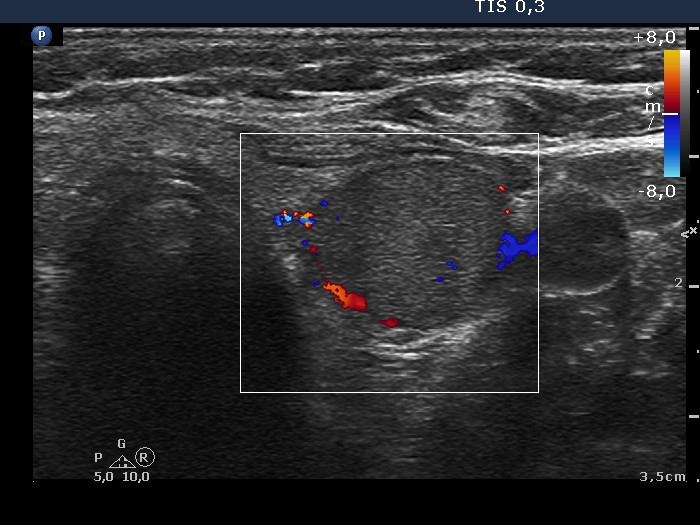

Lower part of the left lobe, transverse scan, color Doppler mode. There are signs of a perinodular blood flow.